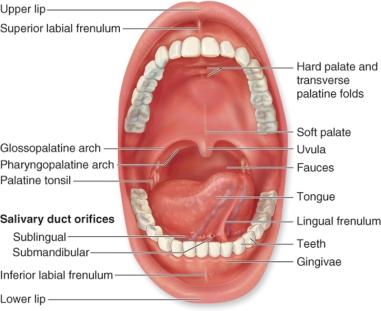

Oral Cavity (Buccal)

8

Hard Palate

9

Soft Palate

10

Rugae of the Hard Palate

11

Vestibule

12

Uvula

13

Deciduous Teeth

baby teeth

14

Permanent Teeth

15

Incisors (8)

Permanent Teeth FRONT

16

Canines (4)

Permanent Teeth

17

Premolars (8)

Permanent Teeth

18

Molars (12)

Permanent Teeth

19

Crown

20

Neck

21

Root

22

Alveoli

23

Gingiva

24

Enamel

25

Dentin

26

Cementum

27

Taste bud

28

Frenulum

29

Papullae

30

Filiform

Papillae

31

Fungiform

Papillae

32

Circumvallate

Papillae